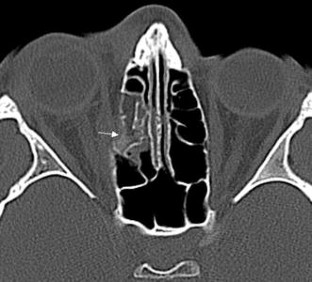

Fig. 1